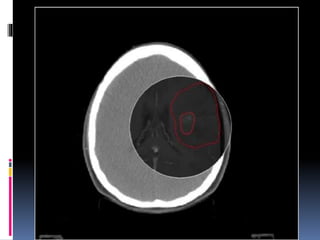

 To enable the clinical oncologist to accurately outline

the area they wish to treat, they might use a

combination of the data from the radiotherapy CT

planning scan and an MRI scan.

 This is often the case with brain tumours and is

called MRI fusion.

 In this image the clinical oncologist is using both MRI

(inner circle) and CT data to outline the tumours in this

patient's brain.

 With some brain tumours the clinical oncologist wants

to treat the area where the tumour was located before

it was taken out (de-bulked) by the surgeon.

 MRI Fusion allows the pre-operative MRI scan to be

overlaid with the post-operative CT planning scan.